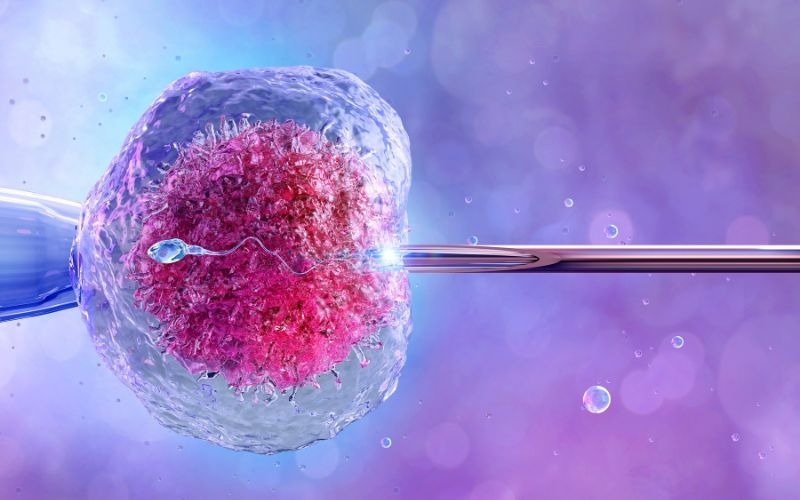

Bone Marrow Transplant

This procedure is used to treat blood-related disorders such as leukemia, lymphoma, and other immune system diseases.